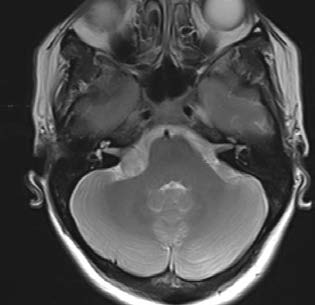

Se practica exploración craneal mediante secciones axiales, sagitales y coronales según protocolo habitual que incluye secuencias ponderadas en T1, T2, FLAIR y estudio de difusión. Se practican cortes de alta resolución centrados en fosa posterior y conductos auditivos internos. Se administra cte.e.v. obteniéndose nuevas secuencias potenciadas en T1.

Parénquima cerebral, cerebelo y troncoencéfalo sin evidencia de lesiones significativas. Lesión sólida en ángulo pontobulbocerebeloso que se introduce en el CAI derecho, de 16 x 22 x 15 mm de diámetros longitudinal, trasnverso y AP respectivamente, con captación intensa de contraste y alguna pequeña zona quítica en su interior que sugiere como 1ª posibilidad meningioma, sin poder descartar schwannoma a este nivel. Sistema ventricular de tamaño y morfología normal, centrado en línea media. No hay signos de sangrado y no se identifica malformación vascular ni patología ocupante de espacio.

Cisternas de la base libres. No hay malformación de base de cráneo. No se observa desplazamiento de las estructuras de la línea media.

Meningioma/schwannoma de ángulo pontobulbocerebeloso derecho con extensión intracanalicular. Pequeño quiste subputaminal derecho de 5 mm.